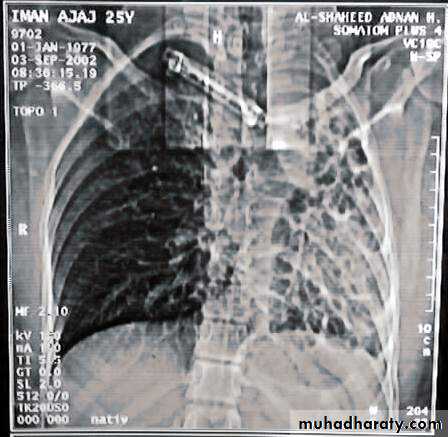

• Chest X-ray ,CT chest ..

• 5-Chest CT is the single non invasive tool for both diagnosing &assessing the severity of the disease .